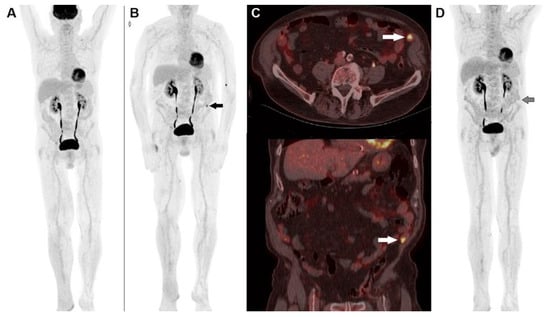

- Sachpekidis, C.; Larribere, L.; Pan, L.; Haberkorn, U.; Dimitrakopoulou-Strauss, A.; Hassel, J.C. Predictive Value of Early 18F-FDG PET/CT Studies for Treatment Response Evaluation to Ipilimumab in Metastatic Melanoma: Preliminary Results of an Ongoing Study. Eur. J. Nucl. Med. Mol. Imaging 2015, 42, 386–396. [Google Scholar] [CrossRef]

- Anwar, H.; Sachpekidis, C.; Winkler, J.; Kopp-Schneider, A.; Haberkorn, U.; Hassel, J.C.; Dimitrakopoulou-Strauss, A. Absolute Number of New Lesions on 18F-FDG PET/CT Is More Predictive of Clinical Response than SUV Changes in Metastatic Melanoma Patients Receiving Ipilimumab. Eur. J. Nucl Med. Mol. Imaging 2018, 45, 376–383. [Google Scholar] [CrossRef]